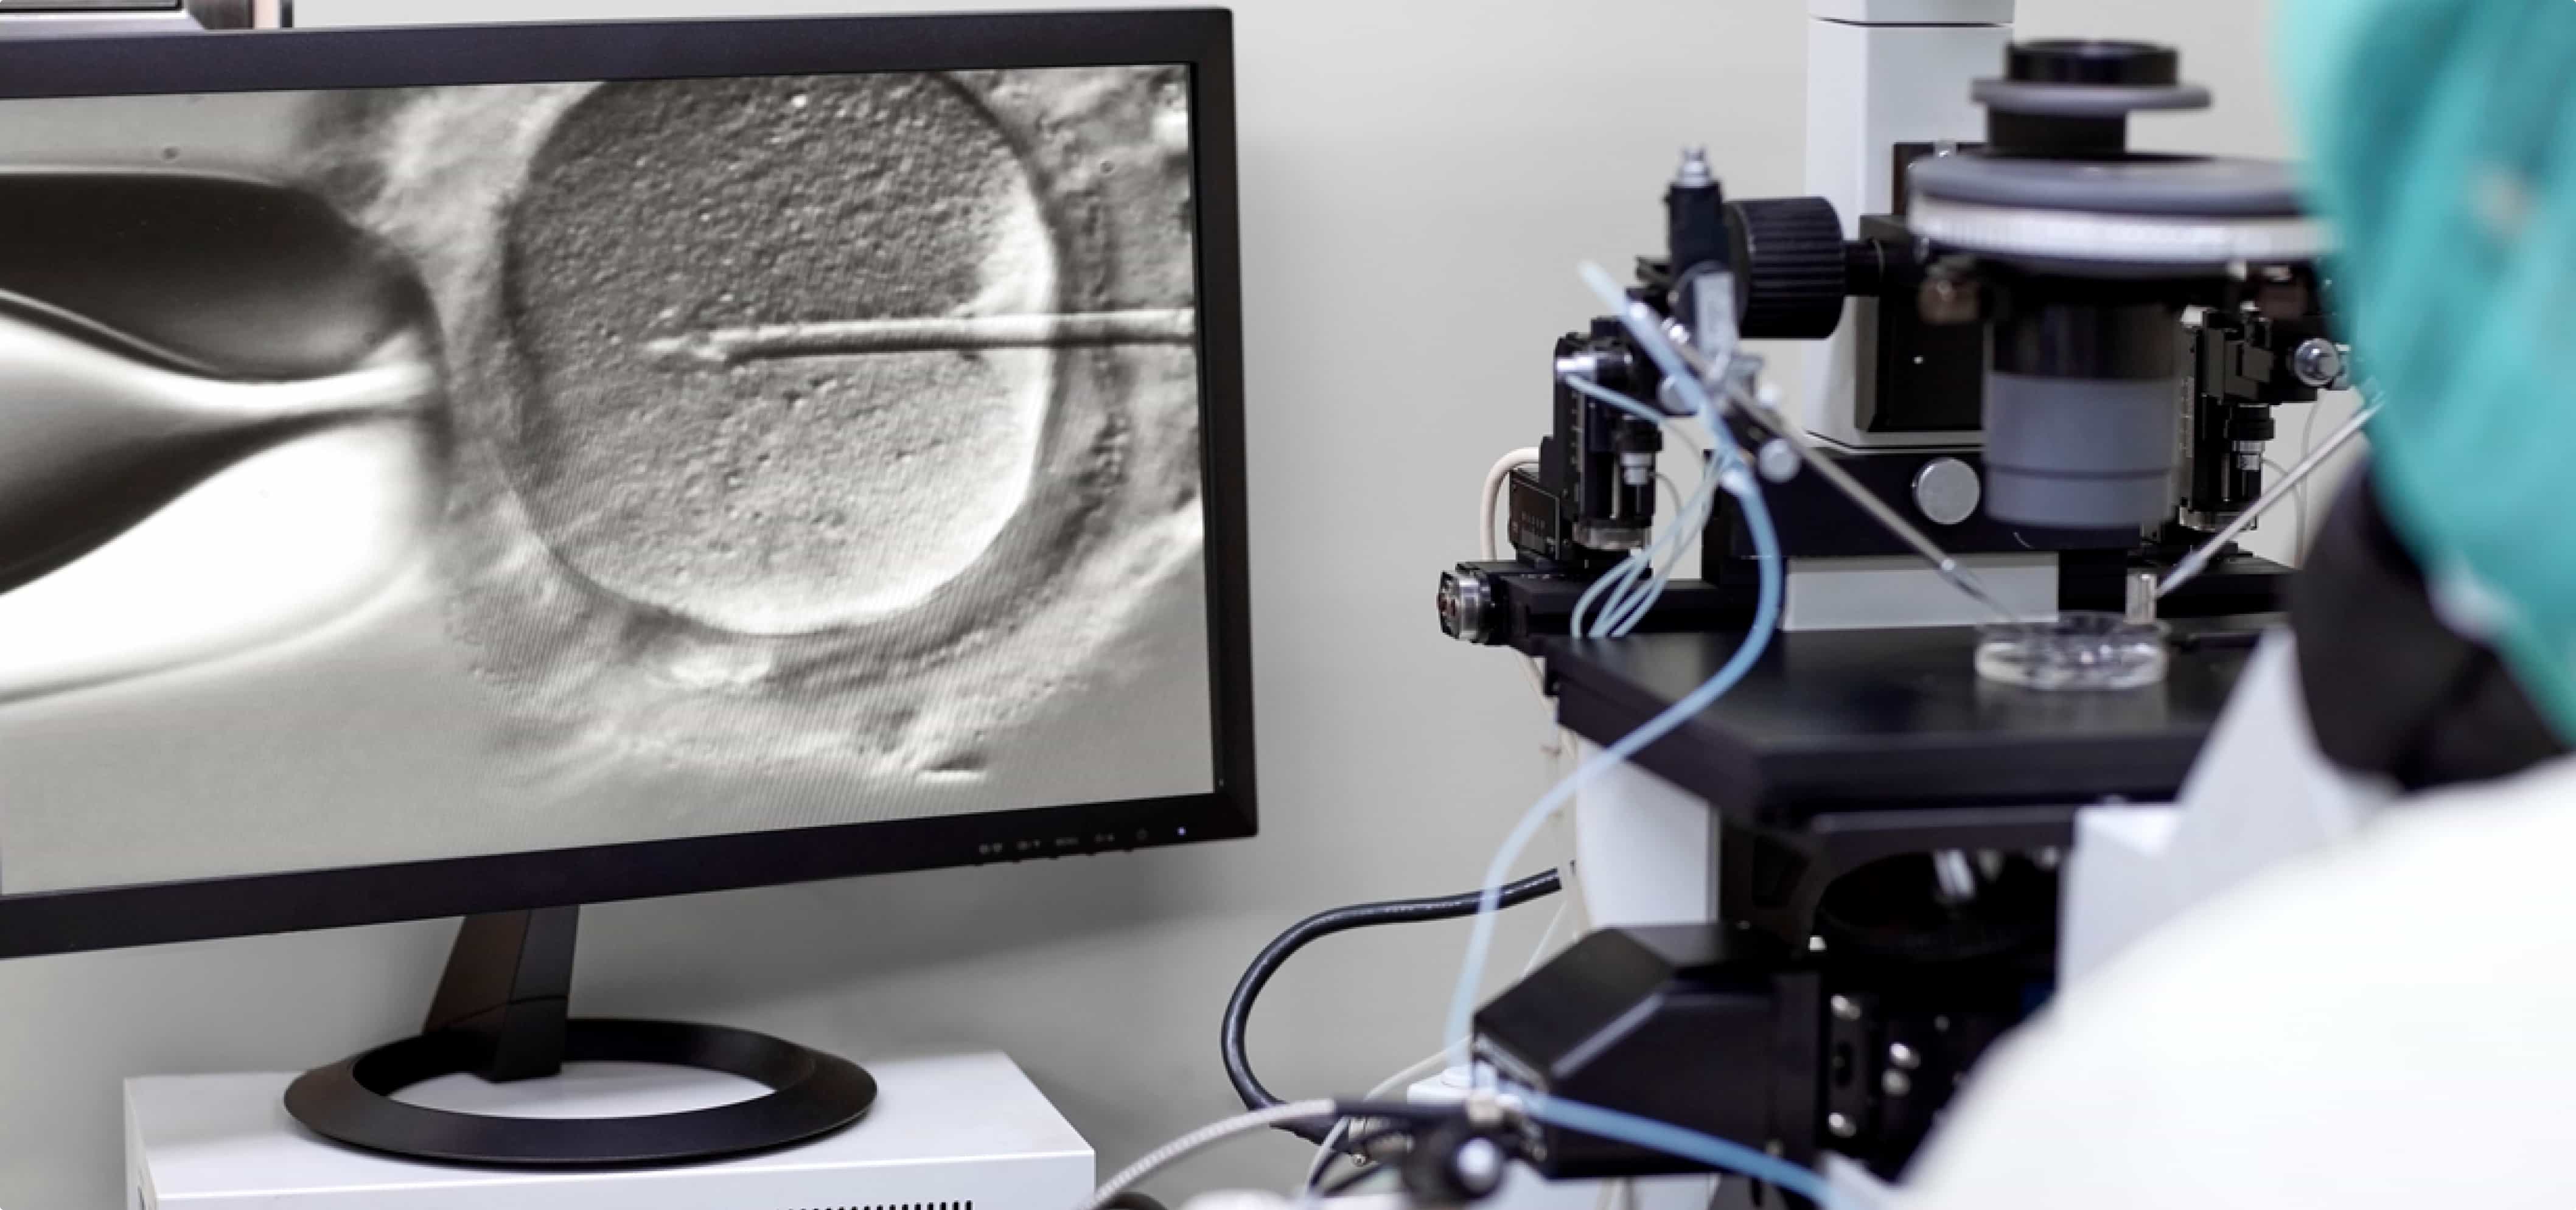

In-Vitro Fertilisation

Commonly known as IVF, In-Vitro Fertilisation is a popular assisted conception method. It involves taking hormone medications or injections to stimulate the ovaries to produce more eggs than usual. These eggs are then extracted and fertilized with a sperm sample to create embryos. Finally, the embryos are transferred to the uterus.

A standard IVF cycle

After the stimulation stage, eggs are collected from you or your egg donor.

With your sperm or donor’s sperm, the eggs are fertilized in the embryology lab to form embryos.